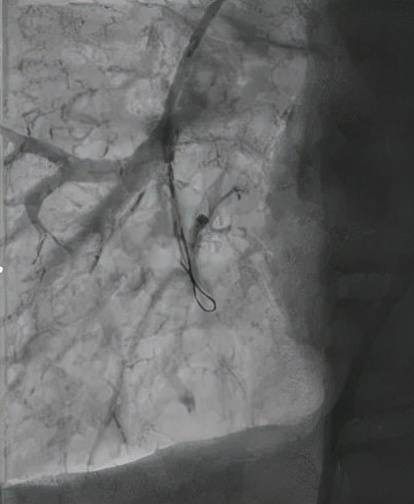

△导丝进入狭窄的肺动脉造影,明确病变血管

△送入OCT(光学相干断层成像)导管进行血管扫描,明确血管病变为网格样的慢性血栓